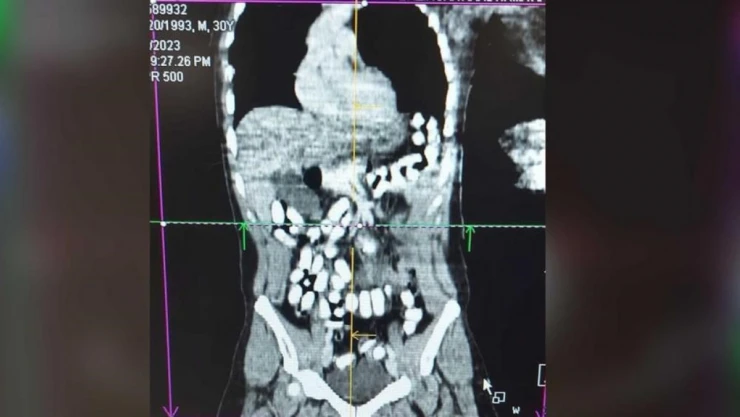

Erzincan İl Emniyet Müdürlüğü Narkotik Suçlarla Mücadele Şube Müdürlüğü ekiplerince, uyuşturucu ve uyarıcı maddelerin imal ve ticareti veya temini, gerek kullanmak için satın alınması, kabul edilmesi veya bulundurulması, gerekse de kullanımının kolaylaştırılması veya özendirilmesi eylemlerine ilişkin yapılan çalışmalarda; Türk Ceza Kanunu 188’inci maddesi “Uyuşturucu veya uyarıcı madde imal ve ticareti” suçuna ilişkin polis uygulama noktasında durdurulan, bir araçta bulunan A. H. isimli İran uyruklu şüpheli alınan iç beden muayenesi kararına istinaden hekim gözetiminde çekilen tomografi neticesinde mide ve bağırsak kısmında 126 adet kapsül halinde daralı ağırlığı ise 977,60 gr Afyon sakızı ve 25 adet Metadon hap ele geçirildi.